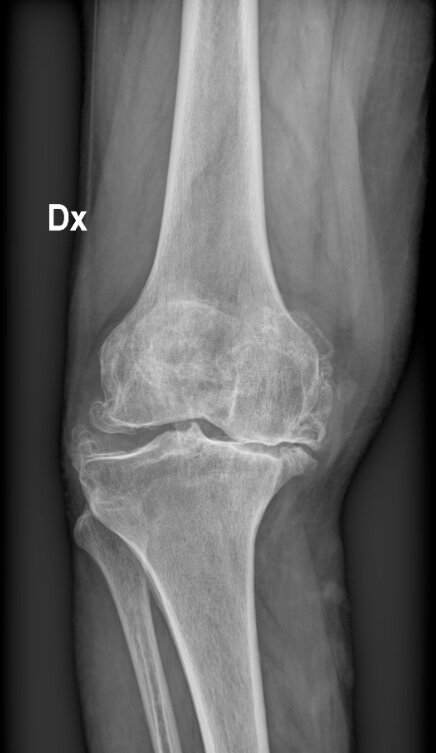

Il Dott. Piergiorgio Pirani rappresenta il punto d’incontro tra la tradizione chirurgica d’eccellenza e le frontiere della medicina moderna. Specialista in Ortopedia e Traumatologia, ha dedicato la sua carriera al ripristino della mobilità articolare, diventando un punto di riferimento nella chirurgia robotica del ginocchio e nella patologia della spalla.